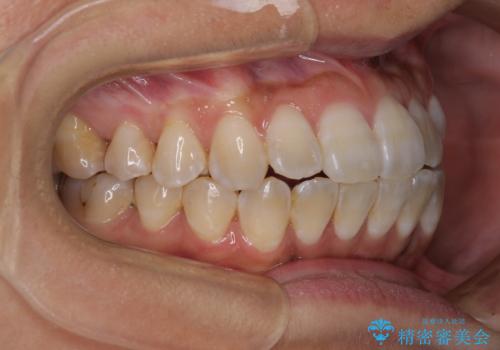

- 上下の前歯のでこぼこを気にして来院された患者様です。

職場の都合により、表側のワイヤー装置や着脱作業が頻繁なマウスピース矯正は困難とのことで、全く目立たない裏側矯正装置を用いて口元を整えることとしました。

途中転勤や出産があり、通院できない期間が長くありましたが、無事に歯列を整えることができました。